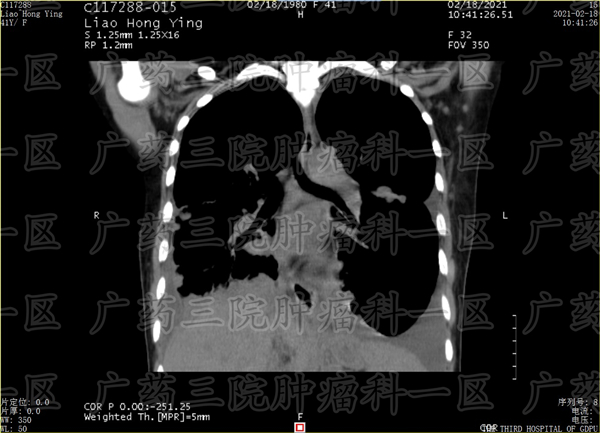

医生需要根据患者的检查报告以及患者的身体状态,会为患者安排多位医生进行多学科会诊,由专家根据患者病情,选择动脉灌注栓塞治疗或粒子植入治疗或消融治疗等技术,制定合适的治疗方案。

根据患者病情不同,可能使用的微创技术不同,广药三院肿瘤科一区医生会为患者安排微创+免疫或微创+中医或其他治疗方案,具体需要根据患者的病情决定。如7月的黄女士,根据她的病情,彭齐荣教授团队医生为其制定了动脉灌注栓塞治疗+免疫治疗的方案,再次检查时,转移的病灶已经得到控制,不在继续增长。下一步医生将继续对病灶进行局部精准控制,以期缩小病灶,缓解副作用。